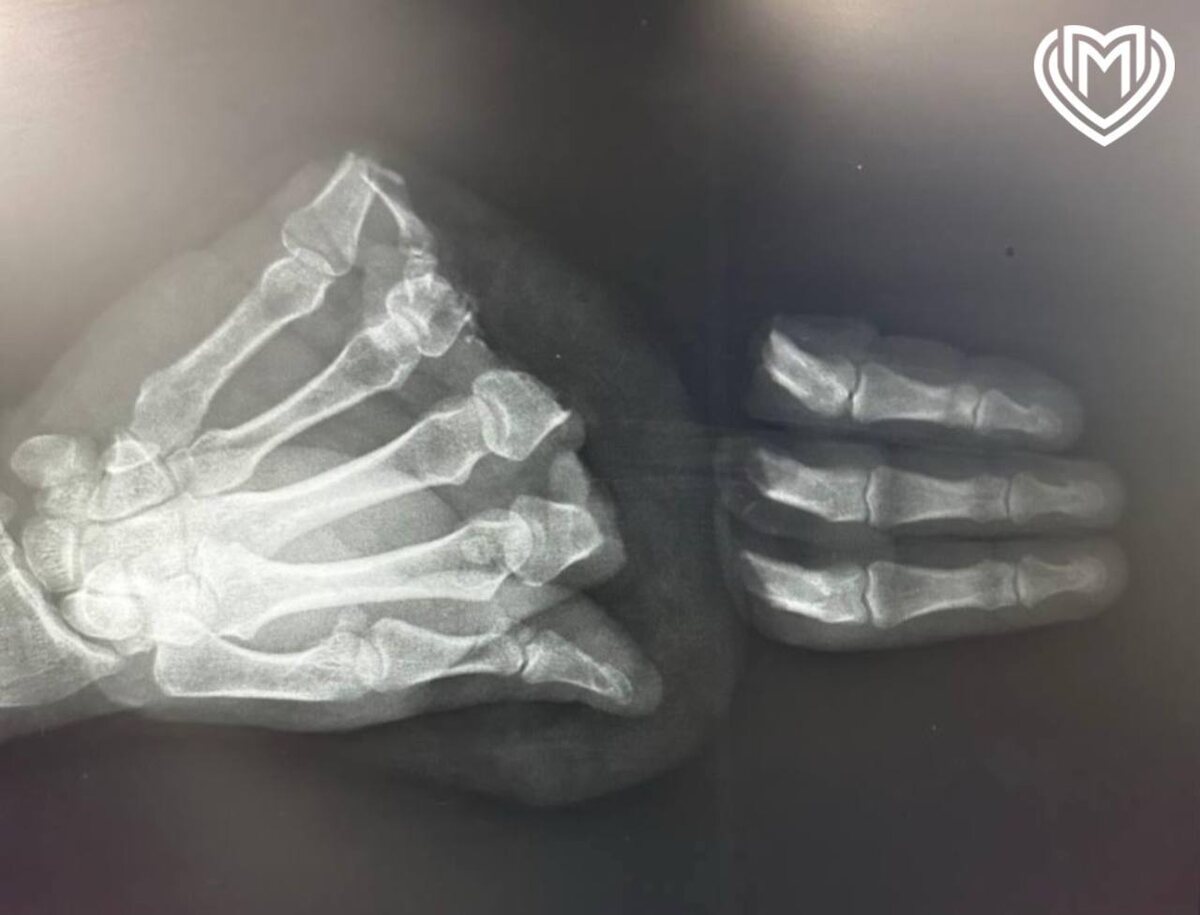

Московские хирурги пришили мужчине отрезанные бензопилой пальцы. Инцидент произошёл в подмосковном Сергиев Посаде. Россиянин занимался домашними делами, но в какой-то момент потерял бдительность и отрезал себе четыре пальца. Мужчину экстренно прооперировали: врачи целых 13 часов спасали руку мужчину и добились своего. Три пальца удалось вернуть, четвертый восстановить было невозможно. Через 10 дней после сложнейшей операции мужчину выписали. ⭕ Подписаться | Прислать новость | Буст

Московские хирурги пришили мужчине отрезанные бензопилой пальцы.

Мужчину экстренно прооперировали: врачи целых 13 часов спасали руку мужчину и добились своего. Три пальца удалось вернуть, четвертый восстановить было невозможно. Через 10 дней после сложнейшей операции мужчину выписали.